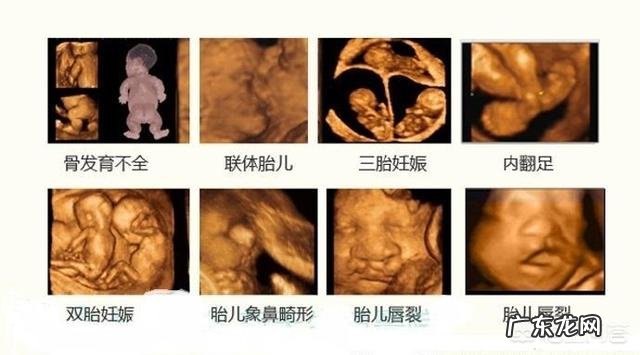

四维彩超是用于观察宫内胎儿的生长发育情况,筛查胎儿畸形,为早期诊断胎儿先天性体表畸形和先天性心脏疾病提供准确的科学依据 。

有些孕妇对于四维彩超存在误解,认为只要孕期做了四维筛查,胎儿就一定不会有畸形 。

其实四维彩超和唐氏儿筛查是两个不同的项目,四维是四维彩超是孕期的大排畸,能排除胎儿脸部和身体的比较明显的表面的畸形,但是唐氏儿是要通过唐氏筛查来排除的,因此,四维通过,胎儿是唐氏儿是可能会出现的情况 。

四维彩超的筛查并不能排除胎儿所有的畸形,比如:先天性心脏病,胎儿的耳朵,听力,视力都不在四维彩超的筛查范围 。